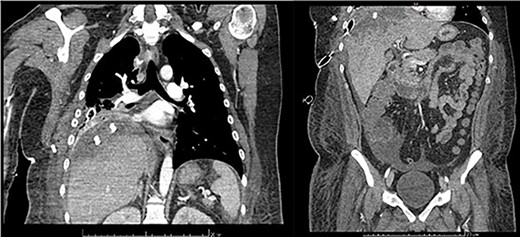

Examination revealed tachycardia, tachypnea, jaundice, dehydration, jugular vein distension, right lung hypoventilation, ascites, upper abdominal tenderness and bilateral lower limb edema. Laboratory workup highlighted neutrophilic leukocytosis, with WBCs exceeding 20 000/μl, along with an abnormal hepatic function panel. The latter showed hypertransaminasemia with ALT predominance over AST (344.7 U/L and 288.5 U/L, respectively), hyperbilirubinemia (10.01 μmol/L) and elevated values of ALP (909.1 U/L) and DHL (709.9 U/L). Of relevance, creatinine elevation (2.11 mg/dl), thrombocytosis (629 × 109/L) and positive D-Dimer (5780 ng/ml) were also noted, so acute kidney injury management and thromboprophylactic measures were initiated. A chest X-ray (CXR) showed a massive right pleural effusion (Fig. 1) and an abdominal ultrasound (US) revealed hepatomegaly with a right nodule (Fig. 2). After further evaluation, tomographic evidence of a right pleural effusion occupying 100% of the lung (Fig. 3) and a 20 cm hypodense, nodular lesion in the right liver (Fig. 4) were identified. These findings were suggestive of an ALA concomitant with an empyema. The patient was admitted into the intensive care unit and prepared for surgery.

Follow-up was uneventful until the ninth day. Although laboratory parameters were normalizing, a contrasted computed tomography (CT) scan showed a subpleural collection of 79 × 34 mm, as well as an heterogenous, hypodense hepatic lesion with wall enhancement (Fig. 5). So, an additional VATS was performed through the anterior incision of the previous pleural tube. Adhesions were removed and a 24 FR Blake drain was positioned at the postero-apical region of the cavity. Other than small amounts of serosanguineous drainage, no relevant findings or events were documented until 9 days after such reintervention. By then, an abdominal US revealed a newly formed abscess on the right convexity of the liver measuring 86.5 cc and containing both hyperechoic and hypoechoic contents, and a 2.6 cm nodule on the V hepatic segment. As there were no clinical or biochemical repercussions, conservative management was initiated and completed successfully.

Frontal thoraco-abdominopelvic CT at 9 days after surgery: subpleural collection of 79 × 34 mm, heterogenous, hypodense hepatic lesion with contrast enhancement on its borders, fluid collection around the liver, paracolic gutters and pelvic cavity.